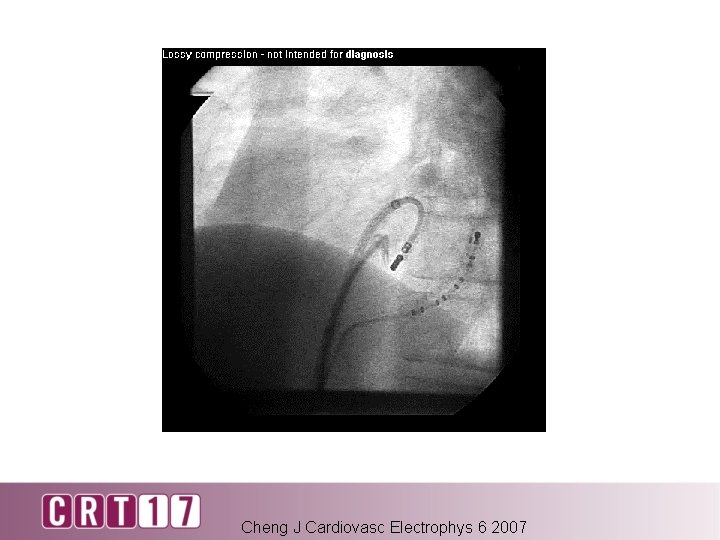

Cheng J Cardiovasc Electrophys 6 2007